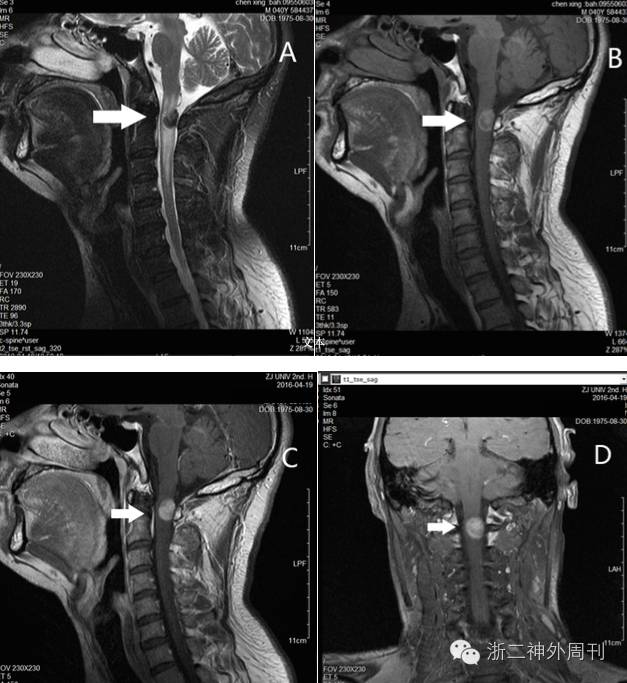

完善术前检查后,全麻下行椎管内病损切除术。术中神经电生理监测下,全椎板切开入路,剪开硬膜,即见黑色肿瘤匍匐于脊髓表面,向内嵌入脊髓深部,呈浸润性生长,与正常脊髓组织边界欠清。脊髓发出神经根处亦被肿瘤浸润包绕。肿瘤质地似橡胶样,切除困难,CUSA效果也不理想,最后使用刀片剜除中心部分肿瘤。术中冰冻提示黑色素性肿瘤,倾向转移性恶性黑色素瘤可能。此外,电生理监测提示肿瘤中心部分切除后电生理阈值略有下降,故仅做部分切除(图2)。术后标本送常规病理检查。

2.术中所见:A.髓内肿瘤匍匐生长于脊髓背侧硬膜,大片黑色素沉积;B. 肿瘤质地极韧,似橡胶样,仅能用刀片剜除;C.神经根受侵犯(箭头);D.肿瘤浸润性生长,与正常脊髓边界不清(箭头),仅部分切除